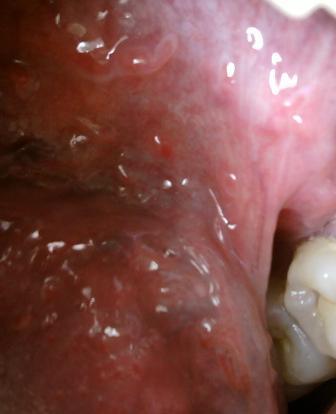

石家庄九州皮肤病医院 > 尖锐湿疣 > > > 治疗尖锐湿疣中医好还是西医好现在尖锐湿疣性病是相当顽固的,同时发病率也是比较高的,所以专家表示:对于疾病的治疗不可以放松警惕,而是应该及时选择相应的治疗方法,坚持治疗,对于疾病的治疗和康复是很关键的。

治疗尖锐湿疣中医好还是西医好目前医学上治疗尖锐湿疣的方法有:西医疗法,中医疗法和药物疗法,西医疗法治疗的特点是见效比较快,但是会复发,中医治疗,减小比较慢,但是可以针对病因进行治疗,能够从身体内部进项调理。不会对人体健康有负面的影响,不同的治疗方法在治疗上是各有利弊的,所以专家表示:应该根据自身病情来选择适合的治疗方法。坚持治疗,疾病是可以达到比较理想的治疗效果的。